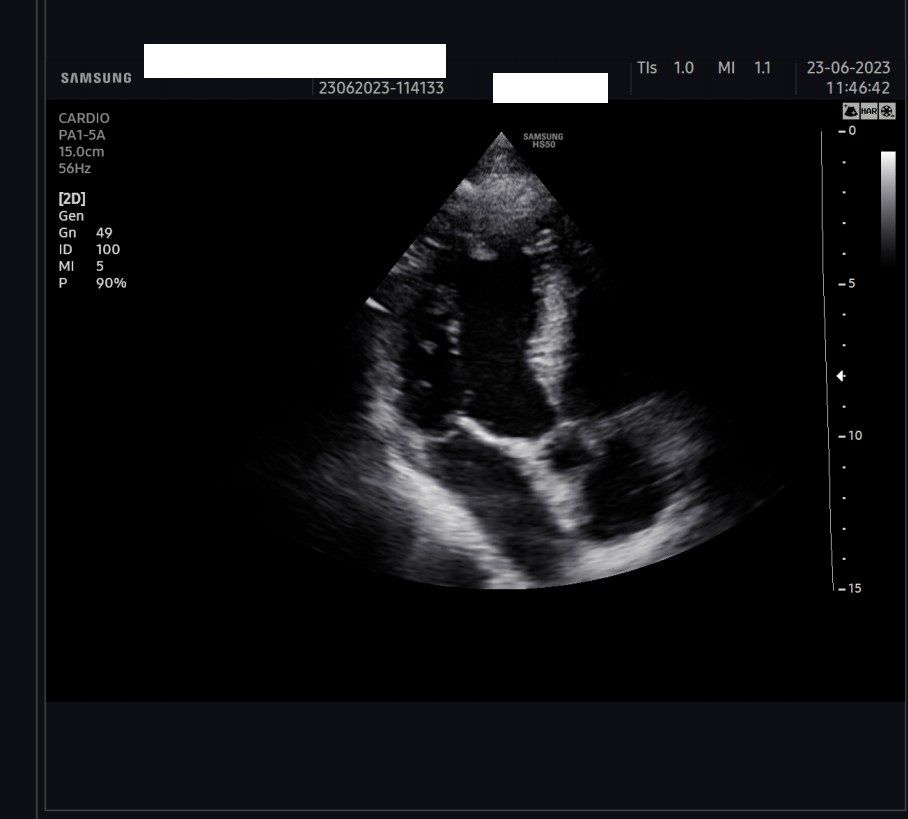

Diploma di maturità classica. Laurea in Medicina e Chirurgia con Lode a 26 anni. Specialista in Oncologia Generale Diagnostica e Preventiva con Lode a 31 anni. Specialista in Malattie Cardiovascolari a 36 anni. Medico generalista dal 1990 poi ospedaliero per trent'anni dal 1993 al 2022 nel corso dei quali ho refertato oltre 100 mila tracciati elettrocardiografici, effettuato oltre 30 mila consulenze specialistiche, praticato circa 10 mila esami ecocardiografici, condotto oltre 2 mila test ergometrici sia su cicloergometro che su treadmill, visionato circa 1500 esami Holter Ecg e ABP ( Ambulatory Blood Pressure ) occupandomi prevalentemente di prevenzione cardiovascolare, ipertensione arteriosa, cardiopatia ischemica, valvulopatie. Dal 2023 ho deciso di trasferire le mie competenze nella libera professione presso il mio studio privato che è stato allestito in linea alle moderne esigenze tecnologiche. Metodiche diagnostiche attualmente praticate: Elettrocardiografia a riposo, Ecocardiografia mono-bidimensionale, PW, CW, Colordoppler tridimensionale, GLS Strain Speckle tracking, Monitoraggio Holter Pressorio delle 24 ore, Monitoraggio Holter ECG 12 canali dinamico delle 24 ore.

Foto e video